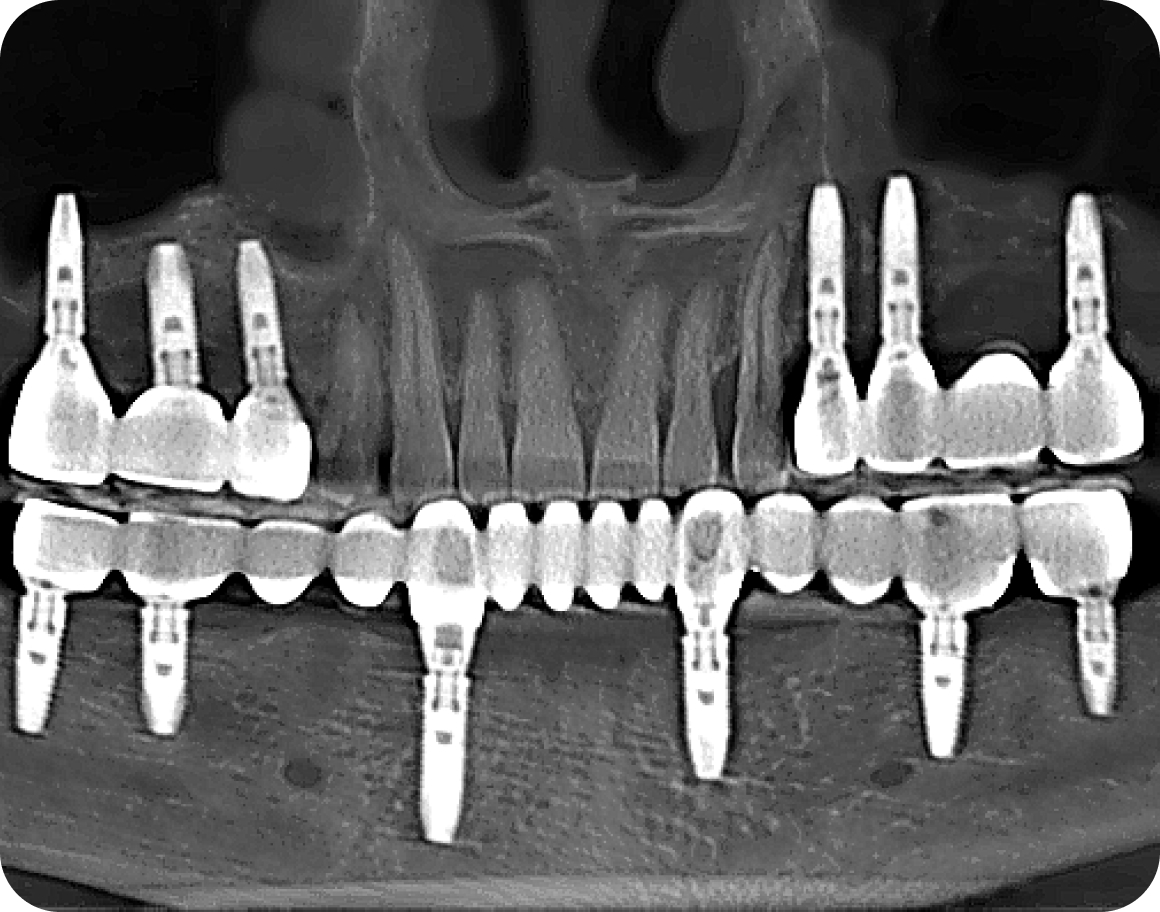

• Компьютерная томография

Установка имплантов

Устанавливаем импланты в правильную позицию в костной ткани, чтобы импланты служили максильно долго и не застревала пища между зубами